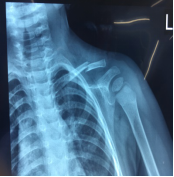

11月份门诊诊疗病例80余人次,病种大多为颈椎病、腰椎间盘突出症、腰椎管狭窄症、梨状肌紧张综合征、胸腰椎小关节紊乱症、小儿髋关节滑膜崁顿、膝关节骨性关节炎、膝关节滑膜炎、肩关节周围炎、股骨头坏死、距骨坏死及桡骨远端骨折、锁骨骨折、尺骨鹰嘴骨折、尺骨骨折、股骨颈骨折、股骨大粗隆撕脱骨折、踝关节骨折、掌骨骨折、指骨骨折、跖骨骨折、趾骨骨折、肩关节脱位等。

手法整复桡骨远端骨折、踝关节骨折、尺骨骨折、掌骨骨折、指骨骨折、跖骨骨折及肩关节脱位、桡骨小头半脱位等各类骨折脱位十余例,行小夹板固定及石膏托外固定十余例。